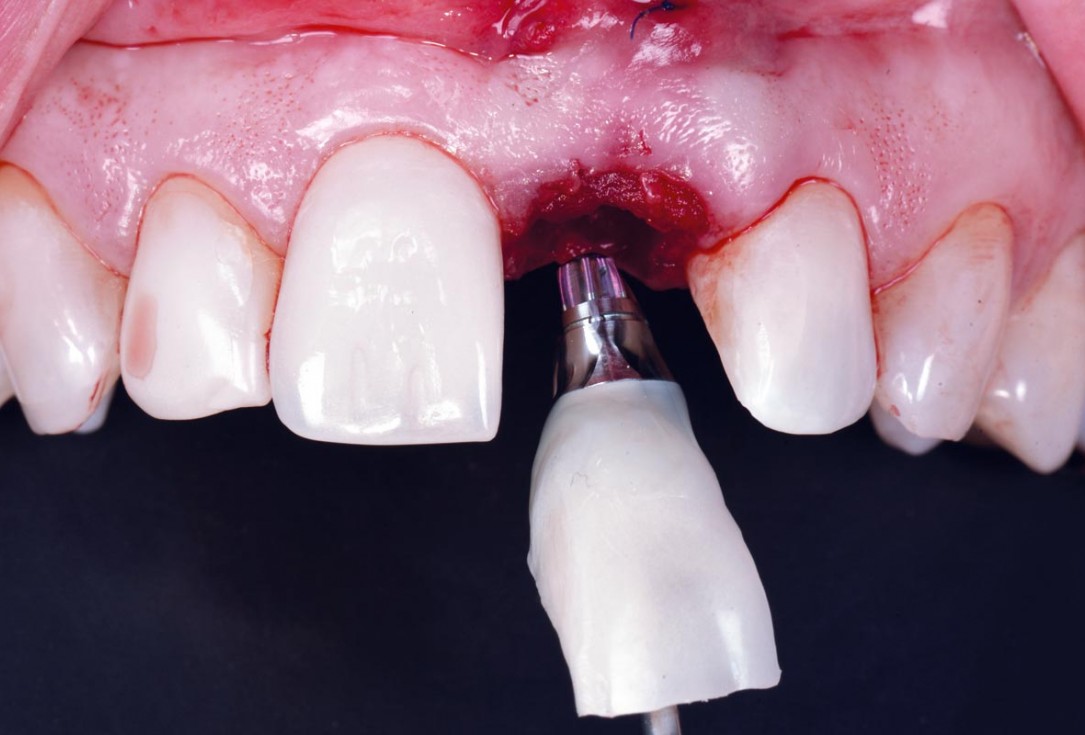

24/30 - Insertion of the immediate temporaryExcellent aesthetic result of buccal augmentation with mucoderm® and maxgraft® after immediate implant placement - 3-years follow-up - Dr. A. Puišys

-